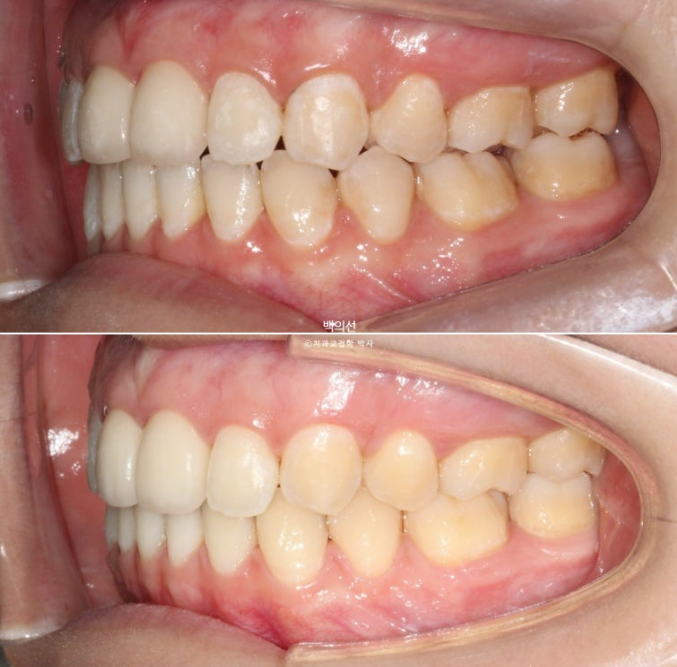

지난 2월 타병원에서 이미 2년 10개월째 클리피씨 발치교정을 진행하던 환자분이 오셨습니다.

교정치료 도중 머리부위에 MRI를 찍을 일이 많이 생겨서 인비절라인으로 치료를 마무리하고 싶어 오셨습니다.

치료기간이 이미 2년 10개월이 된만큼 교정치료 마무리 단계입니다.

인비절라인 장치제작을 위해 클리피씨 장치를 제거한 직후입니다.

아직 맞지 않는 중심선은 남은 공간이 닫히면 자연스레 맞아질 것 입니다.

아까 엑스레이에서 치축이 기울어져 있던 파란화살표 측절치는 튀어나와 보이고 기울어져 보입니다.

25년 3월부터 25년 6월까지 인비절라인 장치 14개를 다 낀 후 모습입니다.

중심선을 잘 맞아졌으며

남아있던 발치공간도 깔끔하게 사라졌습니다.

기울어져 보이던 측절치는 대칭성을 회복했으며

교합은 처음보다 좋아졌습니다.

이제 전후 비교 보겠습니다.

총 치료기간은 4개월입니다.

어금니교합 뿐만 아니라 앞니 교합까지 더 긴밀해졌습니다.

남은 공간이 사라지며 윗니 돌출이 개선되었습니다.